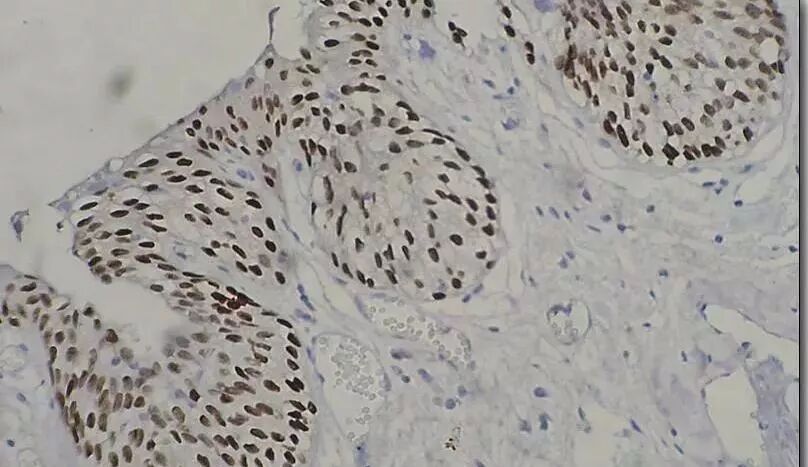

Part 1 免疫组化是什么? 免疫组化,通俗的含义就是把乳腺癌组织中的癌细胞放大到分子级别,看看在这个水平上有哪些跟别的细胞不一样的特征,比如说:有的癌细胞表面会表达一些别的细胞没有的受体蛋白,有的癌细胞所产生的某种蛋白比正常细胞多出很多倍,等等。 举个通俗易懂的比喻,我们对抓到的罪犯进行搜身,看看他们身上都有哪些特征,可能有的身上只拿了一把刀,有的身上拿着定时炸弹。如果癌细胞相当于人体组织中的罪犯,那么免疫组化的标记物则相当于罪犯身上的刀子、炸弹等,很显然拿炸弹的那类罪犯肯定比拿刀子的更危险一些。另外,还可以培训警犬来识别这些罪犯身上特殊物品,让它们帮助我们在更多人群中找到甚至剿灭罪犯——从而治疗肿瘤。 那么,对乳腺癌细胞而言,最重要的免疫组化标记物都哪些呢?这些免疫组化指标又都有些什么含义呢? Part 2 最常用的乳腺癌免疫组化标记物 ER PR Her-2 Ki-67 ER、PR与激素依赖性乳腺癌 ER:雌激素受体 ER( ),阳性提示可以口服药物内分泌治疗,加号越多越好。而ER(-)阴性则说明内分泌治疗可能是无效的。 PR:孕激素受体 PR( )阳性与ER( )的指导意义相似,也提示可以口服药物内分泌治疗,加号也是越多越好。而PR(-)阴性说明内分泌治疗可能无效。 实际上,正常乳腺上皮细胞内依然存在ER、PR表达。当细胞发生癌变时,ER和PR出现部分和全部缺失。如果细胞仍保留ER和(或)PR阳性,代表该乳腺癌细胞的生长和增殖仍然受内分泌的调控,称为激素依赖性乳腺癌。 如果ER和(或)PR缺失,则该乳腺癌细胞的生长和增殖不再受内分泌的调控,称为非激素依赖性乳腺癌。 当ER、PR两者同时( )则预后最好,可以术后或术前使用内分泌治疗。 如果一个阳性一个阴性,雌激素阳性(ER )要好于孕激素阳性(PR )。而且内分泌治疗依然有效。 但若两者都是阴性(-)则说明不受激素调控,那么预后最差——这类罪犯没有弱点、不受控制。 Her-2与乳腺癌靶向治疗 人表皮生长因子受体2(HER2),这个指标在免疫组化领域也表示为C-erbB2。 Her-2(-),为乳腺癌组织Her-2 Her-2( ),也就是1个加号,为乳腺癌Her-2轻度表达; Her-2( ),也就是3个加号,的乳腺癌组织为HER2过度表达。 介于之间的Her-2( ),也就是2个加号,则称之为乳腺癌组织Her-2中度表达,这类情况比较复杂,需进一步做分子检测,如荧光原位杂交法(FISH)的方法证实Her-2的基因是否存在扩增,如果FISH阳性,就可以确认存在Her-2过表达。 Her-2(-)与Her-2( )的乳腺癌不需要使用靶向治疗药物(常用为赫赛汀),而Her-2过度表达的乳腺癌则可以选用靶向治疗药物,如赫赛汀等作为一线或二线治疗药物。 Ki-67:肿瘤细胞表达越低越好 Ki-67是一种标记细胞增殖状态的抗原。 Ki-67其功能与有丝分裂密切相关,在细胞增殖中是不可少的,阳性说明癌细胞增殖活跃。 Ki-67的监测多用于判断肿瘤的良、恶性及恶性程度,也用于探讨细胞增殖活性、细胞周期与肿瘤的生长方式、浸润方式、复发、转移等生物学行为及预后的关系。 Part 3 乳腺癌也分A、B、C型 治疗方法大不一样! 在乳腺癌中,联合Ki67指数高低与ER、PR阳性与否,可以对乳腺癌做更细的分类: Luminal A型 ER和(或)PR阳性,Her-2阴性,Ki-67低表达(<14%) 这一亚型几乎不需要化疗,单纯内分泌治疗能达到很好的效果。但要结合临床分期,如淋巴结状况及其他危险因素等综合而定。 Luminal B型(含Her-2过表达者) ER和(或)PR阳性,Her-2阴性,Ki-67高表达(≥14%) ER和(或)PR阳性,Her-2过表达,此时无论Ki-67在任何水平都将乳腺癌界定为Luminal B型 这类亚型一般要选择多种方法的综合治疗方案。 因为存在激素受体的阳性表达,所以内分泌治疗在一定程度上是有效的。但不可避免需要使用其他化疗药物进行辅助,如细胞毒性治疗(紫杉醇、吉西他滨、环磷酰胺、顺铂等)。 若存在Her-2过表达,则可以使用赫赛汀等靶向药治疗。 三阴乳腺癌(TNBC) ER(-)和PR(-)Her-2(-),Ki67高表达(≥14%)。这类乳腺癌不适用内分泌治疗,且预后相对不好。 “三阴乳腺癌”患者和“基底样”患者有近80%的重合,但前者还包含一些特殊组织学类型,如低危(典型)髓样癌及腺样囊性癌。可用基底角蛋白染色有助于判定真正的“基底样”肿瘤。 这类患者没有可用的靶向药,且内分泌治疗常常是无效的,此时可使用细胞毒性治疗(紫杉醇、吉西他滨、环磷酰胺、顺铂等)化疗方案进行治疗。 小总结 ER( )和(或)PR( )阳性可以内分泌治疗,且预后相对好。 Her-2过表达:( )和部分FISH检测为基因扩增的( ),预后相对不好,但条件允许的情况下最好使用靶向治疗药物(赫赛汀)。 最后,Ki67表达越低越好。